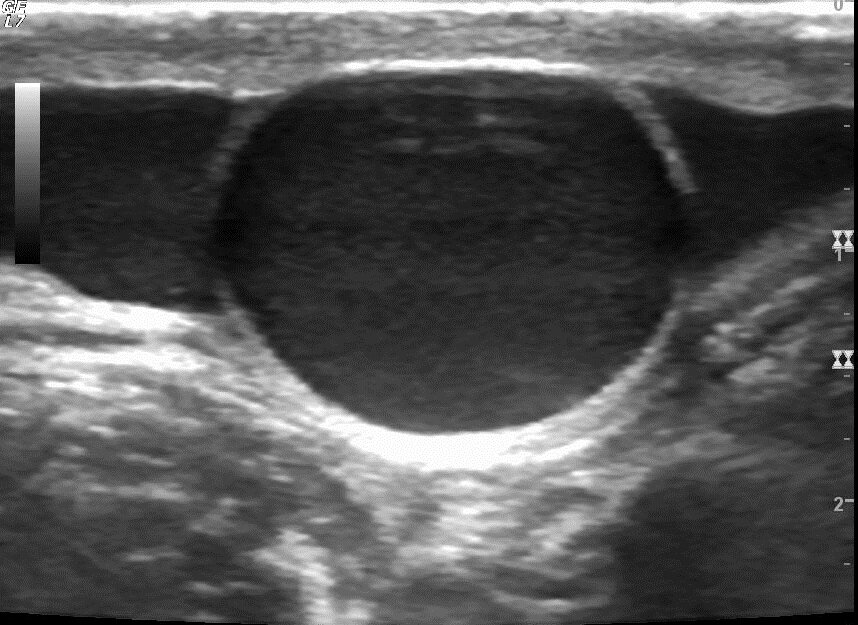

Водянка яичек, гидроцеле

Чаще всего гидроцеле бывает сообщающимся, это когда водичка гуляет туда-сюда, реже бывает клапанное гидроцеле, в этом случае туда идет, а обратно никак, при этом формируется так называемая "напряженная водянка", состояние при котором жидкость в мошонке скапливается под значительным давлением. При этом может происходить сдавление сосудов яичка, что конечно последнему не очень нравится. Кроме того, бывает изолированное гидроцеле, это когда жидкость в мошонке осталась, а трубочка уже заросла. И вот болтается эта жидкость в мошонке, выйти не может и рассосаться из-за большого объема никак. Гидроцеле подлежит оперативному лечению в плановом порядке, исключение напряженная водянка - в этом случае может быть выполнена пункция оболочек для снятия напряжения (то же и при изолированном гидроцеле). Правильнее сроки к проведению операции при гидроцеле определять не по возрасту, а по ультразвуковым показателям прироста объема яичка и скоростным параметрам кровотока яичка. Если эти показатели в динамике ухудшаются, можно делать вывод о нарушении питания яичка и выставлять показания к операции.

Стоит сказать, что существует так же другой вариант водянки. Его можно назвать "взрослым" вариантом, наверное потому, что он чаще встречается у взрослых. Это водянка воспалительная, при таком состоянии жидкость скапливается в мошонке не по причине миграции из брюшной полости, а в связи с усиленной секрецией оболочками самой мошонки. Лечение такой водянки кардинально отличается от сообщающегося гидроцеле. Особый вариант, присущий только детям – комбинированное гидроцеле. Эта ситуация сопровождается и сообщением с брюшной полостью (т.е. присутствует сообщающееся гидроцеле), и в полости самой мошонки есть «раздражитель», вызывающий избыточное выделение экссудата. Таким раздражителем чаще всего выступает гидатида Морганьи. Она достаточно легко поражается при обычных вирусных инфекциях, и в случае если не произошел её некроз, клинические проявления воспаления представлены только водянкой. Но при этом есть патогномоничный симптом на УЗИ, в полости гидроцеле присутствует взвесь. Выполнение операции при комбинированном гидроцеле не может ограничиваться только перевязкой влагалищного отростка брюшины, поскольку очень вероятно будет рецидив гидроцеле, важно удалить саму гидатиду. Важно! Любой операции на органах репродуктивной системы должно предшествовать ультразвуковое исследование.